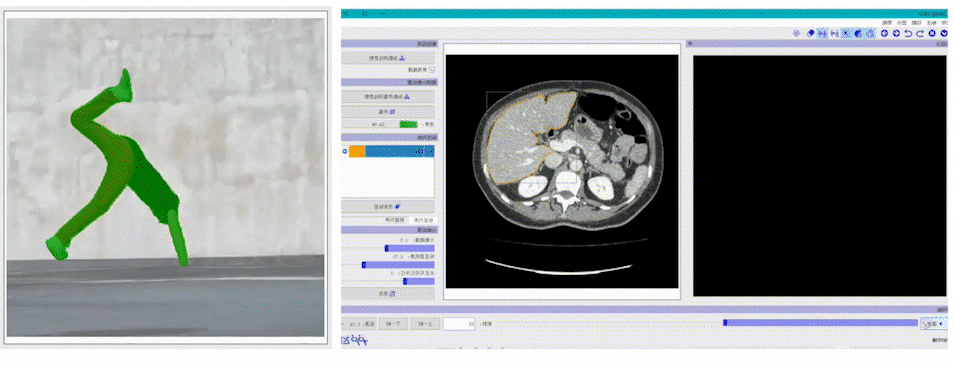

EISeg针对特定数据集进行训练并获得了高质量的交互式分割模型,目前覆盖的场景包括: 医疗腹腔多器官、椎骨分割、产品瑕疵分割、遥感建筑物分割等 。 同时,针对不同场景的标注需求,EISeg提供了相应的特色标注能力,比如遥感图像支持遥感信息的读取,医疗图像支持窗宽窗位的选择等,从而拓展了交互式分割的应用领域。

EISeg正式版视频标注工具以 交互式分割算法 及 交互式视频分割算法MiVOS 为基础,涵盖了通用、腹腔多器官,CT椎骨等不同方向的高质量交互式视频分割模型,方便开发者快速实现视频的分割标注。